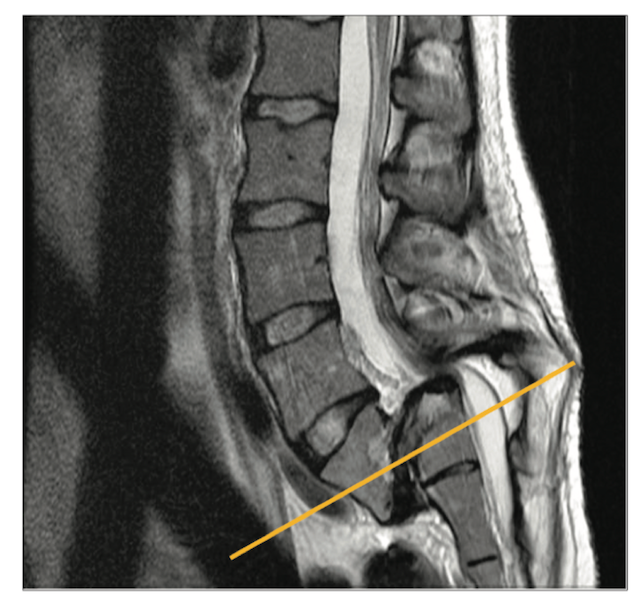

La columna vertebral es una estructura muy fuerte. Cuenta con tres curvaturas naturales encargadas de soportar nuestro cuerpo. Está compuesta de una serie de huesos llamados vértebras, que están unidos entre sí por cartílagos. Esto es lo que nos da la flexibilidad para estirarnos, doblarnos, caminar y mantener el equilibrio. Cualquier alteración en alguna de estas curvaturas o huesos, pueden llevarnos a sentir severos dolores de espalda que en algunas ocasiones se acompañan de cambios físicos. Es por ello que debemos mantener una rutina continua de ejercicios y estiramiento, aunque sólo podamos dedicarle 10 min de nuestro día. Debemos recordad que muchas veces la falta de tiempo es nuestro principal enemigo para la salud. Dedicarse 10 min al día, para mejorar nuestra higiene postural y ejercitarnos debería formar parte de nuestro estilo de vida.

En el Instituto de Cirugía de Columna estamos especializados en el tratamiento global de la patología de la columna vertebral. En el siguiente listado podrás profundizar sobre las diversas patologías y tratamientos que ponemos a tu disposición.